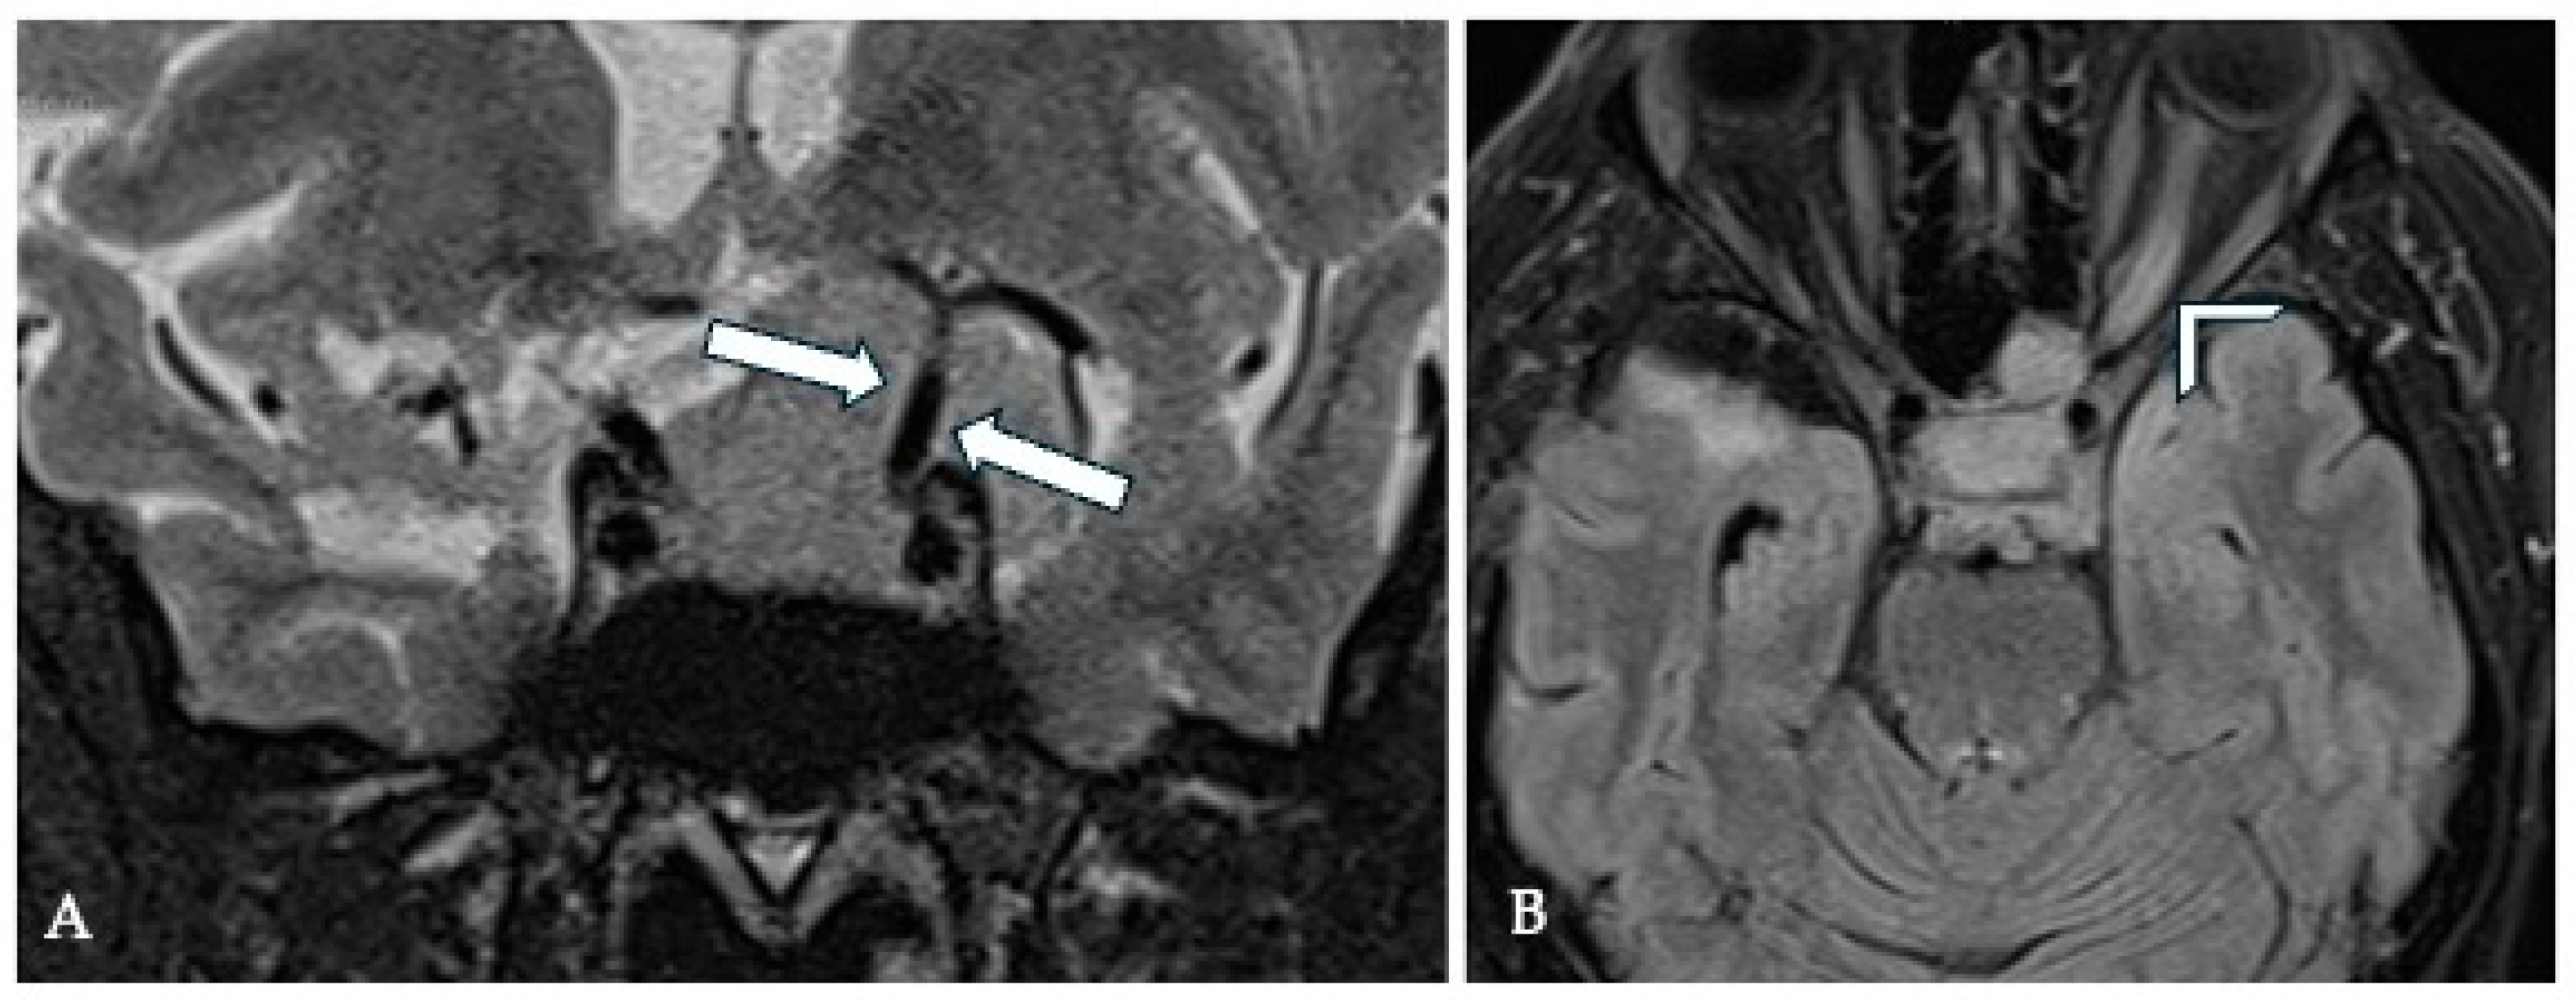

7. Optic Canal Involvement (OCI) and Optic Nerve (ON) Compression

7.1. Surgical Significance

7.2. Imaging Evaluation

7.3. Key Surgical Considerations